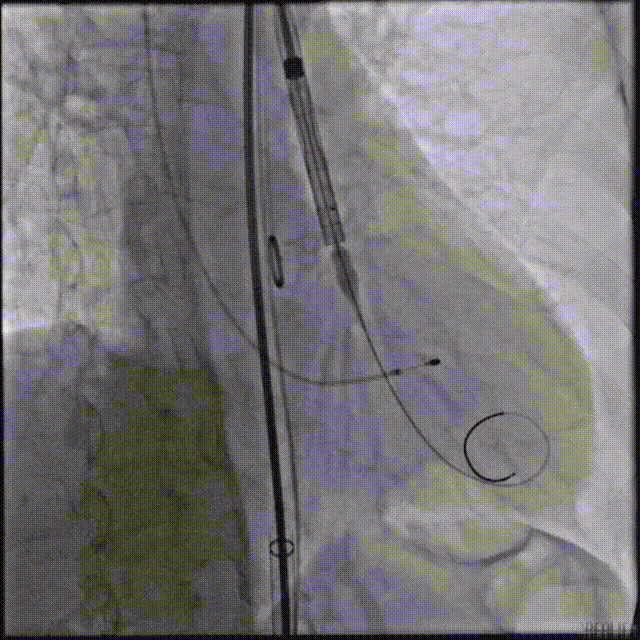

TaurusElite输送系统轻松过弓、跨瓣,AV23瓣膜瓣环上约2-4mm释放。

瓣膜初始位置释放

回收再定位释放

第一次释放到工作位后瓣膜下滑,回收调整位置后选择高位再次释放,最终造影显示瓣膜形态、位置良好,冠脉血流灌注正常,超声提示少量瓣周漏。